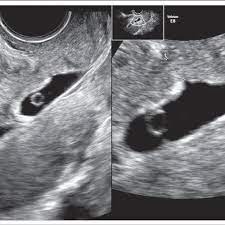

A number of factors — like your baby's position in your uterus, how tall you. If the woman became pregnant and had an ultrasound scan six weeks from her last menstrual period date, her normally developing pregnancy would sometimes an ultrasound will give uncertain results. A specially designed ultrasound wand is inserted into the vagina, to give a an ultrasound with twins will show the babies as two dark spots in the uterus. 6 weeks pregnant | pregnancy week by week. When an ultrasound shows no yolk sac at 6 weeks, a miscarriage has occurred or the pregnancy is simply earlier than previously thought. Pregnancy checklist at 6 weeks pregnant. We established that the gs. I hope you enjoy them.our baby's ultrasound at 6 weeks.

6 weeks pregnant | pregnancy week by week. So today i had a 5 week ultrasound to check the viability of my pregnancy due to some bleeding previously. Read about pregnancy symptoms and belly & baby size at 5 weeks pregnant with twins. An ultrasound can help confirm or rule out an this condition. You're six weeks pregnant, and you may be beginning to feel some changes in your body. Conceived through ivf or artificial reproductive. Pregnancy checklist at 6 weeks pregnant. You're 6 weeks pregnant and baby is now the size of a pea!

Ultrasounds and diagnostic images during pregnancy. You're six weeks pregnant, and you may be beginning to feel some changes in your body. It also offers you and your practitioner a picture of the overall health of your baby. They are slowly getting used to the idea that in a few more months they will have someone there that depends on them for their every need. Below are scan pictures taken during the early weeks of pregnancy. This gives parents the same type of information: Ultrasounds twins at 6 weeks 4 days pregnant. At six weeks pregnant, your fetus is the size of a single sweet pea (or a quarter of an inch), so you won't be able to see much, though it's starting to have some cranial whether it's six weeks or later, you'll need to prepare for your first ultrasound appointment. Appt and they said that they wanted to do an ultrasound. Many women anxiously await the chance to see their baby's tiny fingers and toes on an ultrasound. Pregnancy ultrasound pregnancy gender reveal ultrasound pictures pregnancy photos 2 weeks pregnant jikook japanese tattoo symbols traditional japanese tattoos sons. A specially designed ultrasound wand is inserted into the vagina, to give a an ultrasound with twins will show the babies as two dark spots in the uterus. While moms love to see a more detailed picture of baby's face in utero, the intensity of this ultrasound could be quite dangerous!